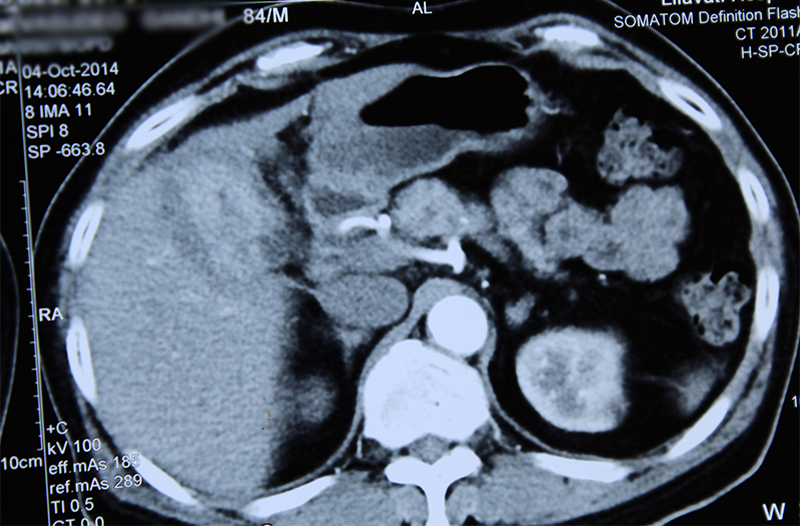

Complex Cholecystitis (xanthogranuloma) or gall bladder cancer

84 year old gentleman with a suspicious gall bladder- liver mass, gall stones & mild jaundice was operated. Biopsies and blood tumor marker levels (CA19-9) were normal on multiple occasions. Hence a decision of surgery was taken after counseling the family. Repeat biopsy was done during the surgery. It also showed only inflammation. Hence the entire mass including gall bladder, portion of liver, part of colon, lymph nodes and bile duct was removed. The final histopathology showed xanthogranulomatous cholecystitis; a pathology that mimics cancer. The patient is now 90 year old.

Gall stones and associated chronic inflammation of gall bladder is a high risk factor for gall bladder cancer especially in Indian patients. However sometimes the chronic inflammation leads to thickening of walls, a mass formation, narrowing of bile ducts, jaundice, appearance of cancer on CT scan / MRI. Except that it may not be cancer. This situation is more seen in patients with advanced age as in our patient who has the stones and ongoing inflammation over many years. However middle aged patients with longstanding stone disease may also have the same issue.